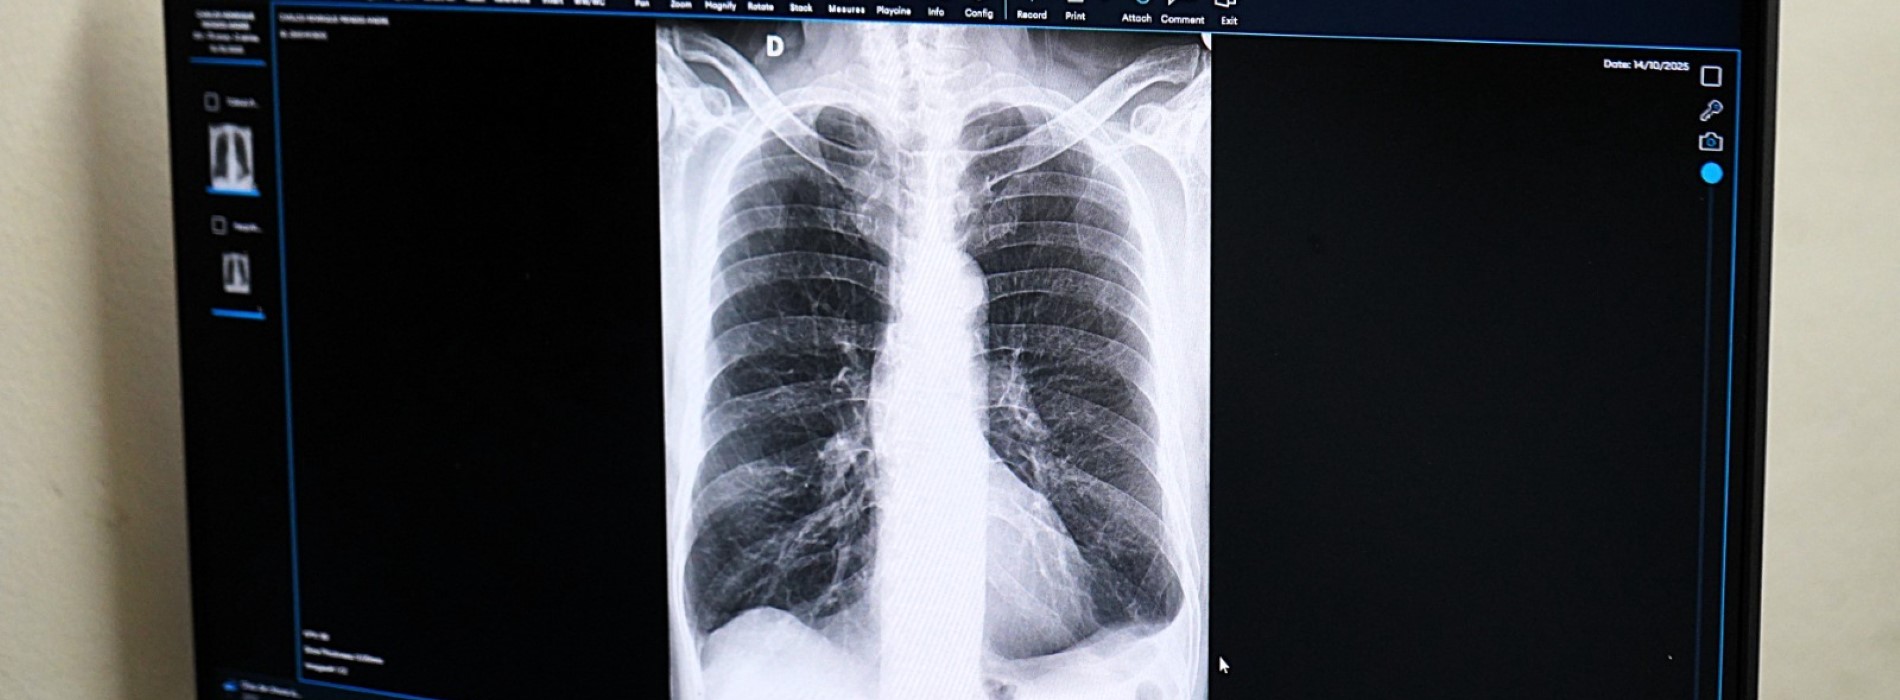

A Prefeitura de Volta Redonda alcançou a marca de mais de 50 mil exames analisados com o apoio da Inteligência Artificial (IA) na rede pública de saúde. O resultado é fruto de um projeto inovador implantado em parceria com a empresa HarpiAI, que vem transformando a rotina médica e qualificando o atendimento prestado à população.

A tecnologia está presente nos hospitais São João Batista (HSJB) e Dr. Munir Rafful (HMMR), Dr. Nelson dos Santos Gonçalves (HNSG) e na UPA (Unidade de Pronto Atendimento) Santo Agostinho, atuando no suporte à análise de exames de radiografia, especialmente em contextos de urgência e emergência. Na prática, a IA funciona como uma segunda opinião diagnóstica.

Os exames seguem o fluxo normal das unidades de saúde e são automaticamente enviados para análise da ferramenta, que retorna em até cinco minutos com o diagnóstico que auxilia os médicos na tomada de decisão. O processo ocorre sem a necessidade de alterações na infraestrutura existente.

A tecnologia permite, ainda, a classificação automática dos exames por nível de prioridade – baixa, moderada e alta – contribuindo para a organização da fila de atendimento, conforme a gravidade dos casos. Até o momento, 44% dos exames analisados foram considerados normais, 31% classificados como de prioridade moderada e 25% como de alta prioridade.